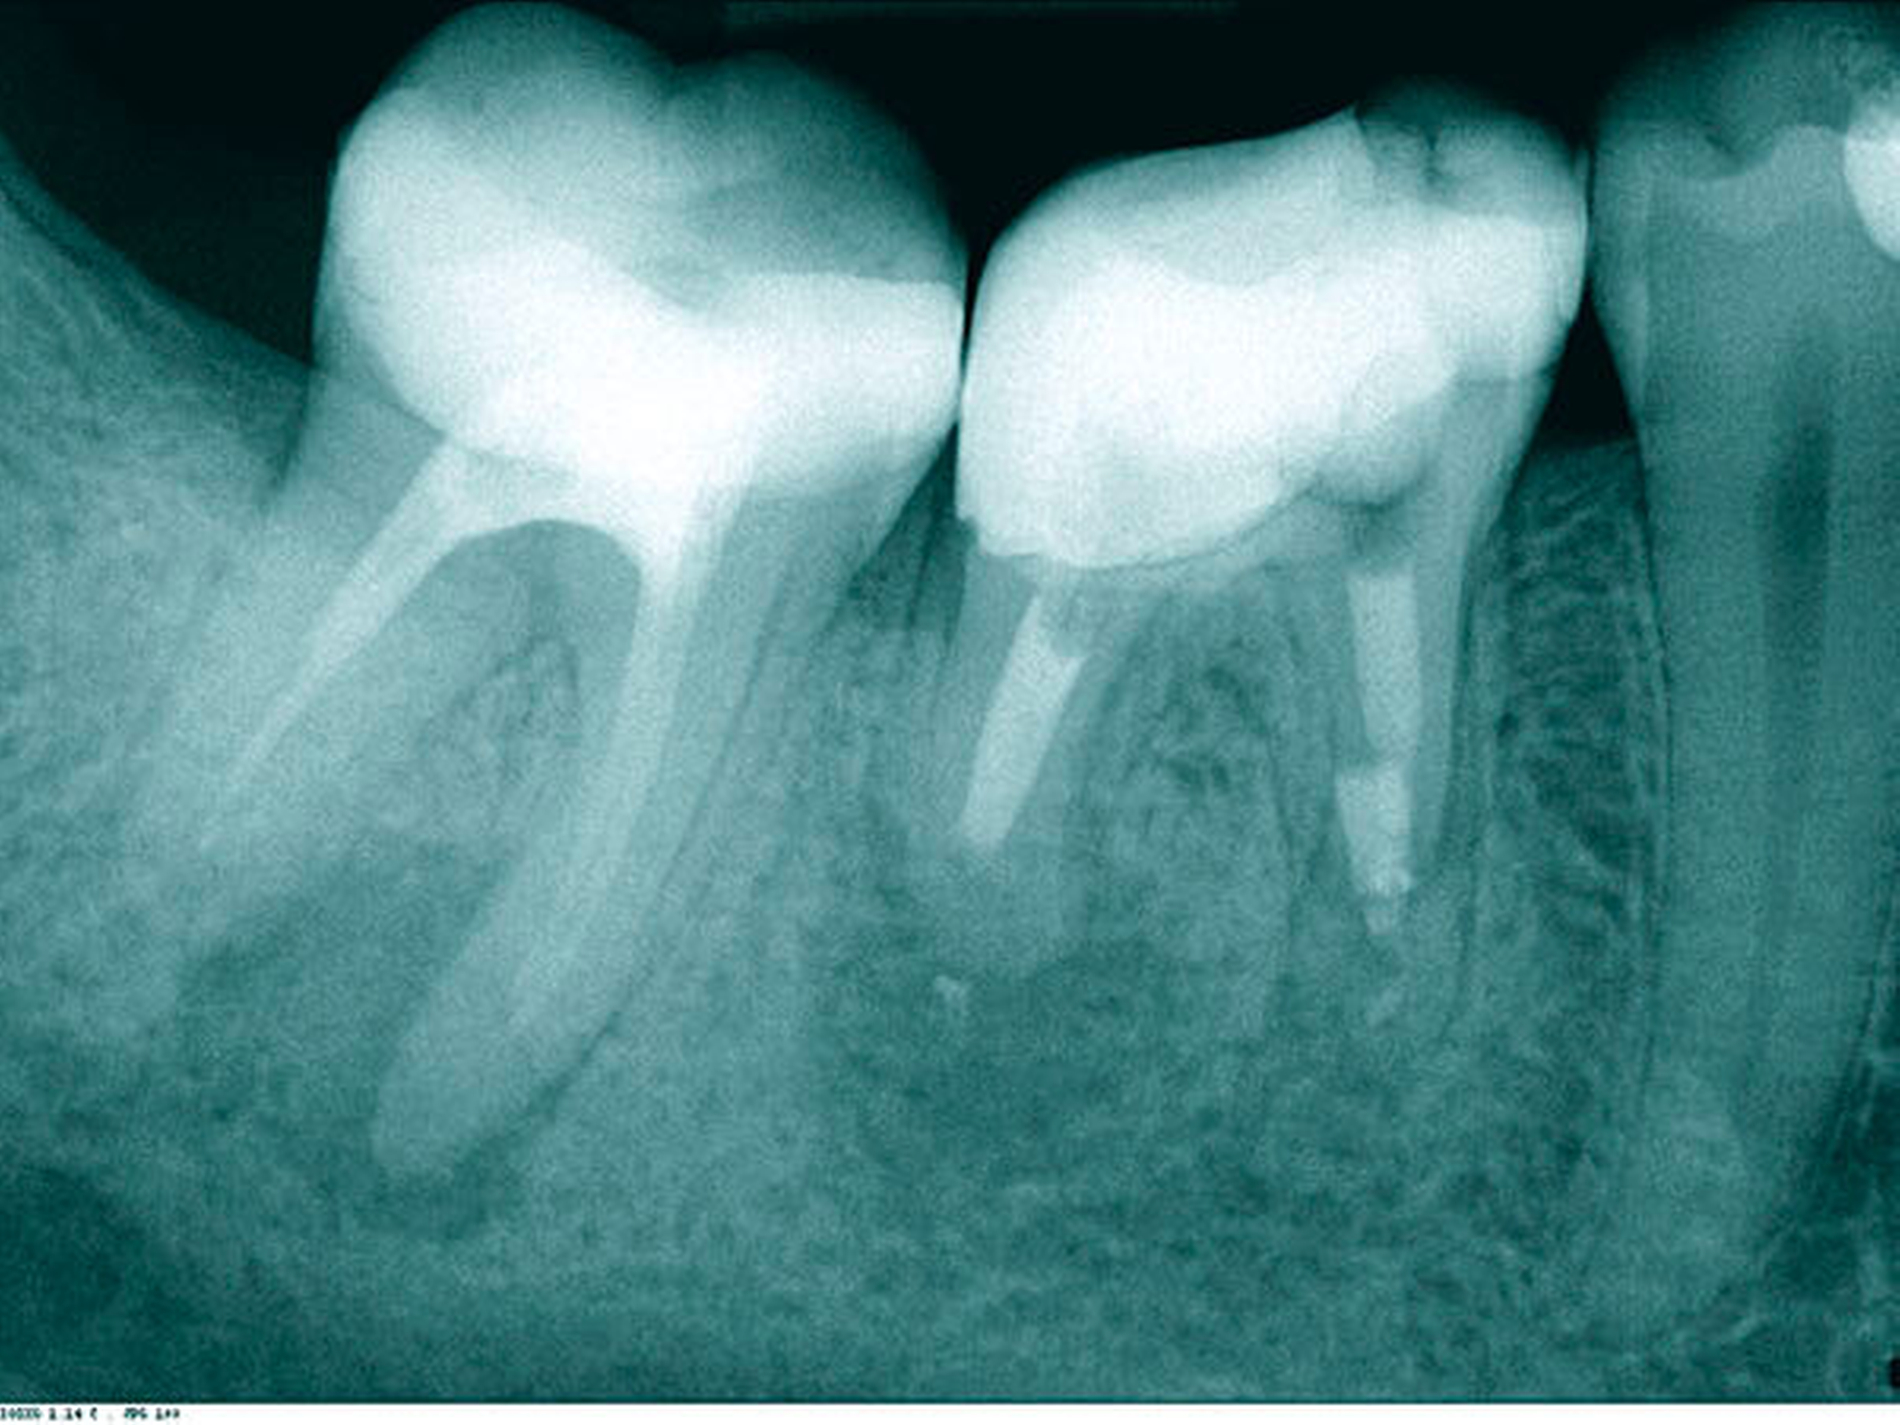

Ein 52-jähriger Patient wurde für die Revision des Zahnes 46 überwiesen. Zum Zeitpunkt der Überweisung klagte der Patient über diffuse, sporadisch auftretende Schmerzen und eine leichte Empfindlichkeit beim Aufbeißen und auf Perkussion. Der Zahn war vor 15 Jahren reseziert worden, die Krone war sieben Jahre alt. Das präoperativ angefertigte Röntgenbild zeigte eine insuffiziente Wurzelkanalfüllung mit apikaler Aufhellung an beiden resezierten Wurzelspitzen. Die mesiale Wurzel wies nur einen abgefüllten Kanal auf, in der distalen Wurzel war ein Wurzelstift aus Metall zur Verankerung eingebracht (Abbildung 1).